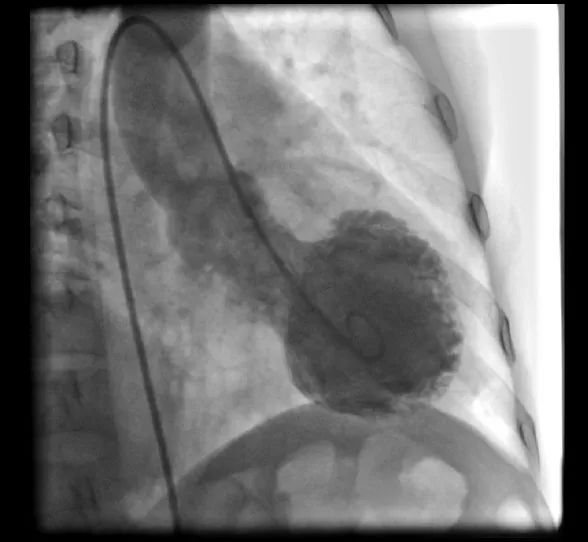

好的故事总是一波三折,这个病例也不例外,计划内的冠脉造影阴性,前降支、右冠和回旋支均未见明显狭窄(图2)。

图2:患者冠脉造影未见明显异常。

此时我们回忆起患者家属曾补充这样一个病史,患者心悸和胸痛发作前2小时,和其儿子发生过剧烈争吵!于是,在患者冠脉造影阴性之后,我们立刻进行了另外一个造影——左室造影,左室造影提示心尖呈球囊样扩张(图3),此时真凶——应激性心肌病终于浮出水面。

图3:左室造影提示心尖球囊样扩张。